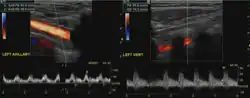

Diagnosis

The evaluation for this condition includes: